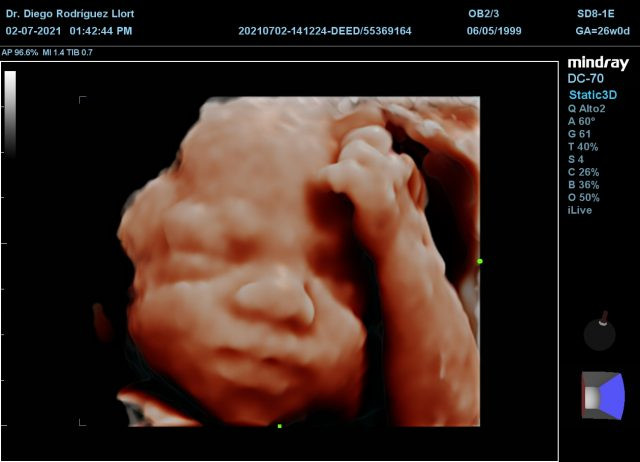

• Ultrasonido 3D y 4D: Las ecografías en tres dimensiones y cuatro dimensiones permiten ver de forma más clara al bebé, otorgándole volumen y movilidad en el 4D.

• Ultrasonido 5D: La ecografía 5D es capaz de realizar una reconstrucción más definida y realista del feto. La nueva generación de ecógrafos de alta resolución incrementa de manera decisiva la capacidad diagnóstica y la detección de malformaciones fetales.